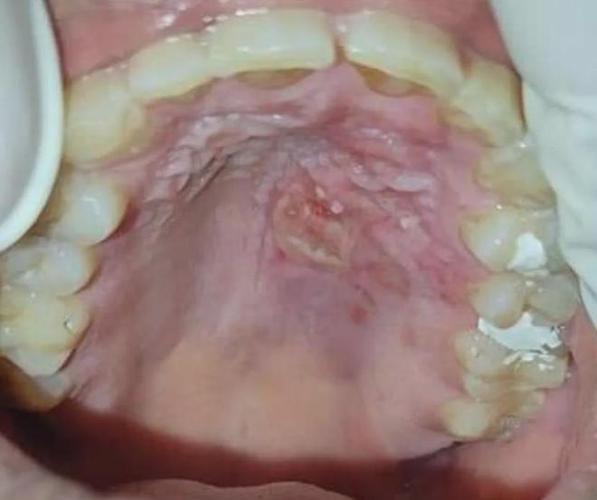

普通的小溃疡(如“轻型口疮”)通常比较小,7-10天会自愈,您描述的“好大一块”,在医学上更可能是以下两种情况之一:

- 重型口疮(阿弗他溃疡):也叫“复发性坏死性黏膜腺周围炎”,特点是溃疡面积大(直径可达1-2厘米甚至更大),边缘整齐,但基底凹陷,像一个小坑,疼痛感非常剧烈,愈合时间也长,通常需要1-4周甚至更久,愈合后可能会留下疤痕。

- 疱疹性口炎:由单纯疱疹病毒引起,初期可能是成簇的小水疱,很快会破溃,形成一片糜烂面或浅表溃疡,看起来就像“烂了一大块”,这种溃疡面积可能很广,除了牙龈、上颚,甚至可能出现在舌头和嘴唇上,并可能伴有发烧、淋巴结肿大等全身症状。